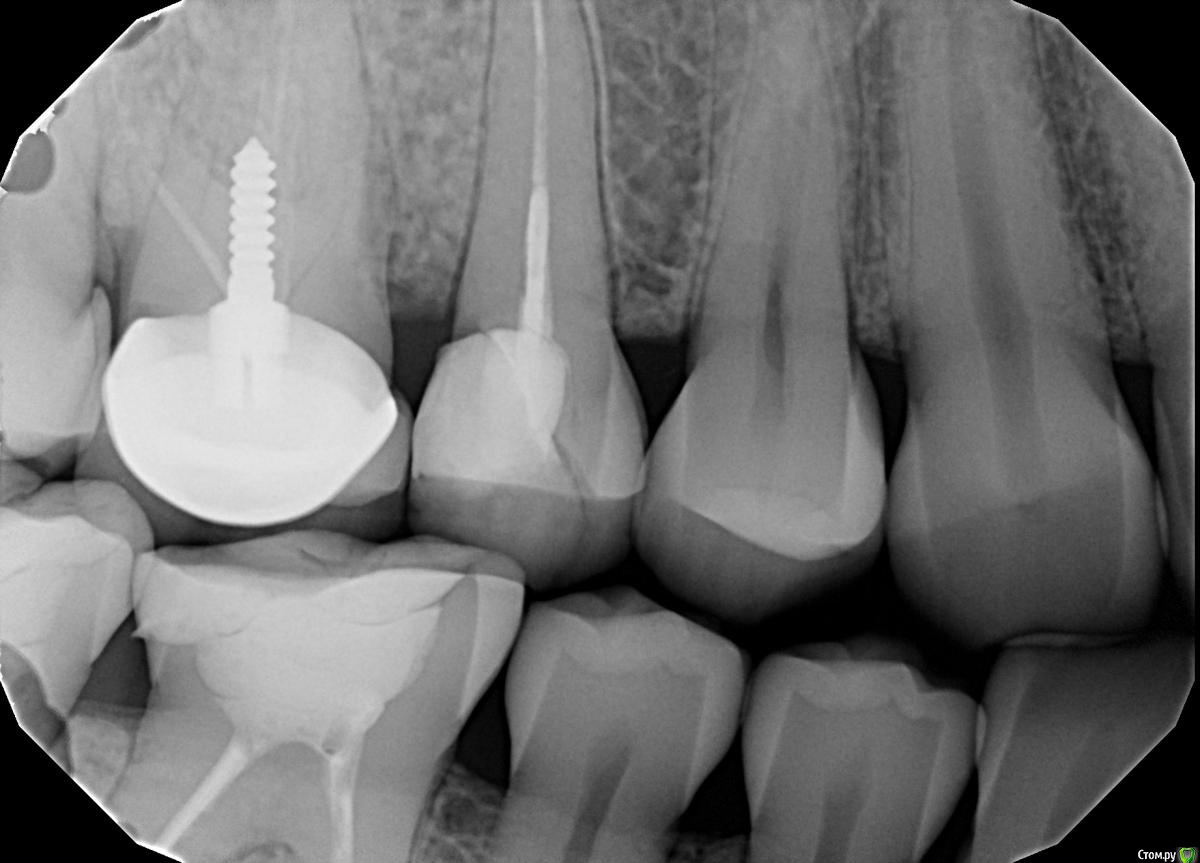

Сломался 15 верхний справа.

Сломанную часть удалили.

Как мне сказали шансов спасти почти нет.

post-6232-0-65126600-1478030675_thumb.jpg

зуб думаю в принципе спасабельный только придется с десной повозиться и затем запротезировать, в 1.6 надо каналы перелечить

По поводу 1.6? Это рядом с ним который под коронкой? Надо перелечивать каналы? В обще, у меня это уже второй зуб, который сломался. Первый зуб сломался как раз соседняя шестерка. В 2010 году. Вот теперь пятый. Как жалею, что во время никто не убедил покрыть коронкой эту пятерку (ведь в зоне улыбки уже).